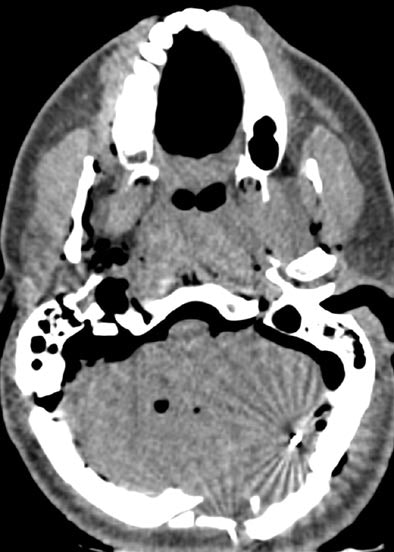

| Features of a gunshot wound to the head at virtual autopsy. Top and below, transverse CT images of a lethal gunshot wound to the head show multiple calvarial fractures, posterior settling of the brain, and pneumocephalus. Metallic fragments and foci of gas are present in the left cerebellum (below). A distinct linear bullet track is not present. Bottom, 3D volume-rendered image of the skull shows the comminuted fracture of the posterior skull. Republished with permission of the Radiological Society of North America from Radiology (August 2006, Vol. 240:2, pp. 522-528); published online before print as 10.1148/radiol.2402050972. |

Of 78 wound tracks, 10 (13%) were not seen at MDCT, the group reported. The missed tracks included six upper extremity wounds and four thigh wounds. In two cases, however, findings missed at autopsy (fracture of the cervical spine, bullet fragments in the posterior area of the neck) were identified at MDCT.

"We have shown that virtual autopsy with multidetector CT can aid prediction of lethal wound and fragment localization in victims with high-velocity gunshot wounds," the authors concluded. "Single gunshot wound tracks are well-defined. The major limitation occurs in classifying and identifying intersecting and co-mingling tracks."